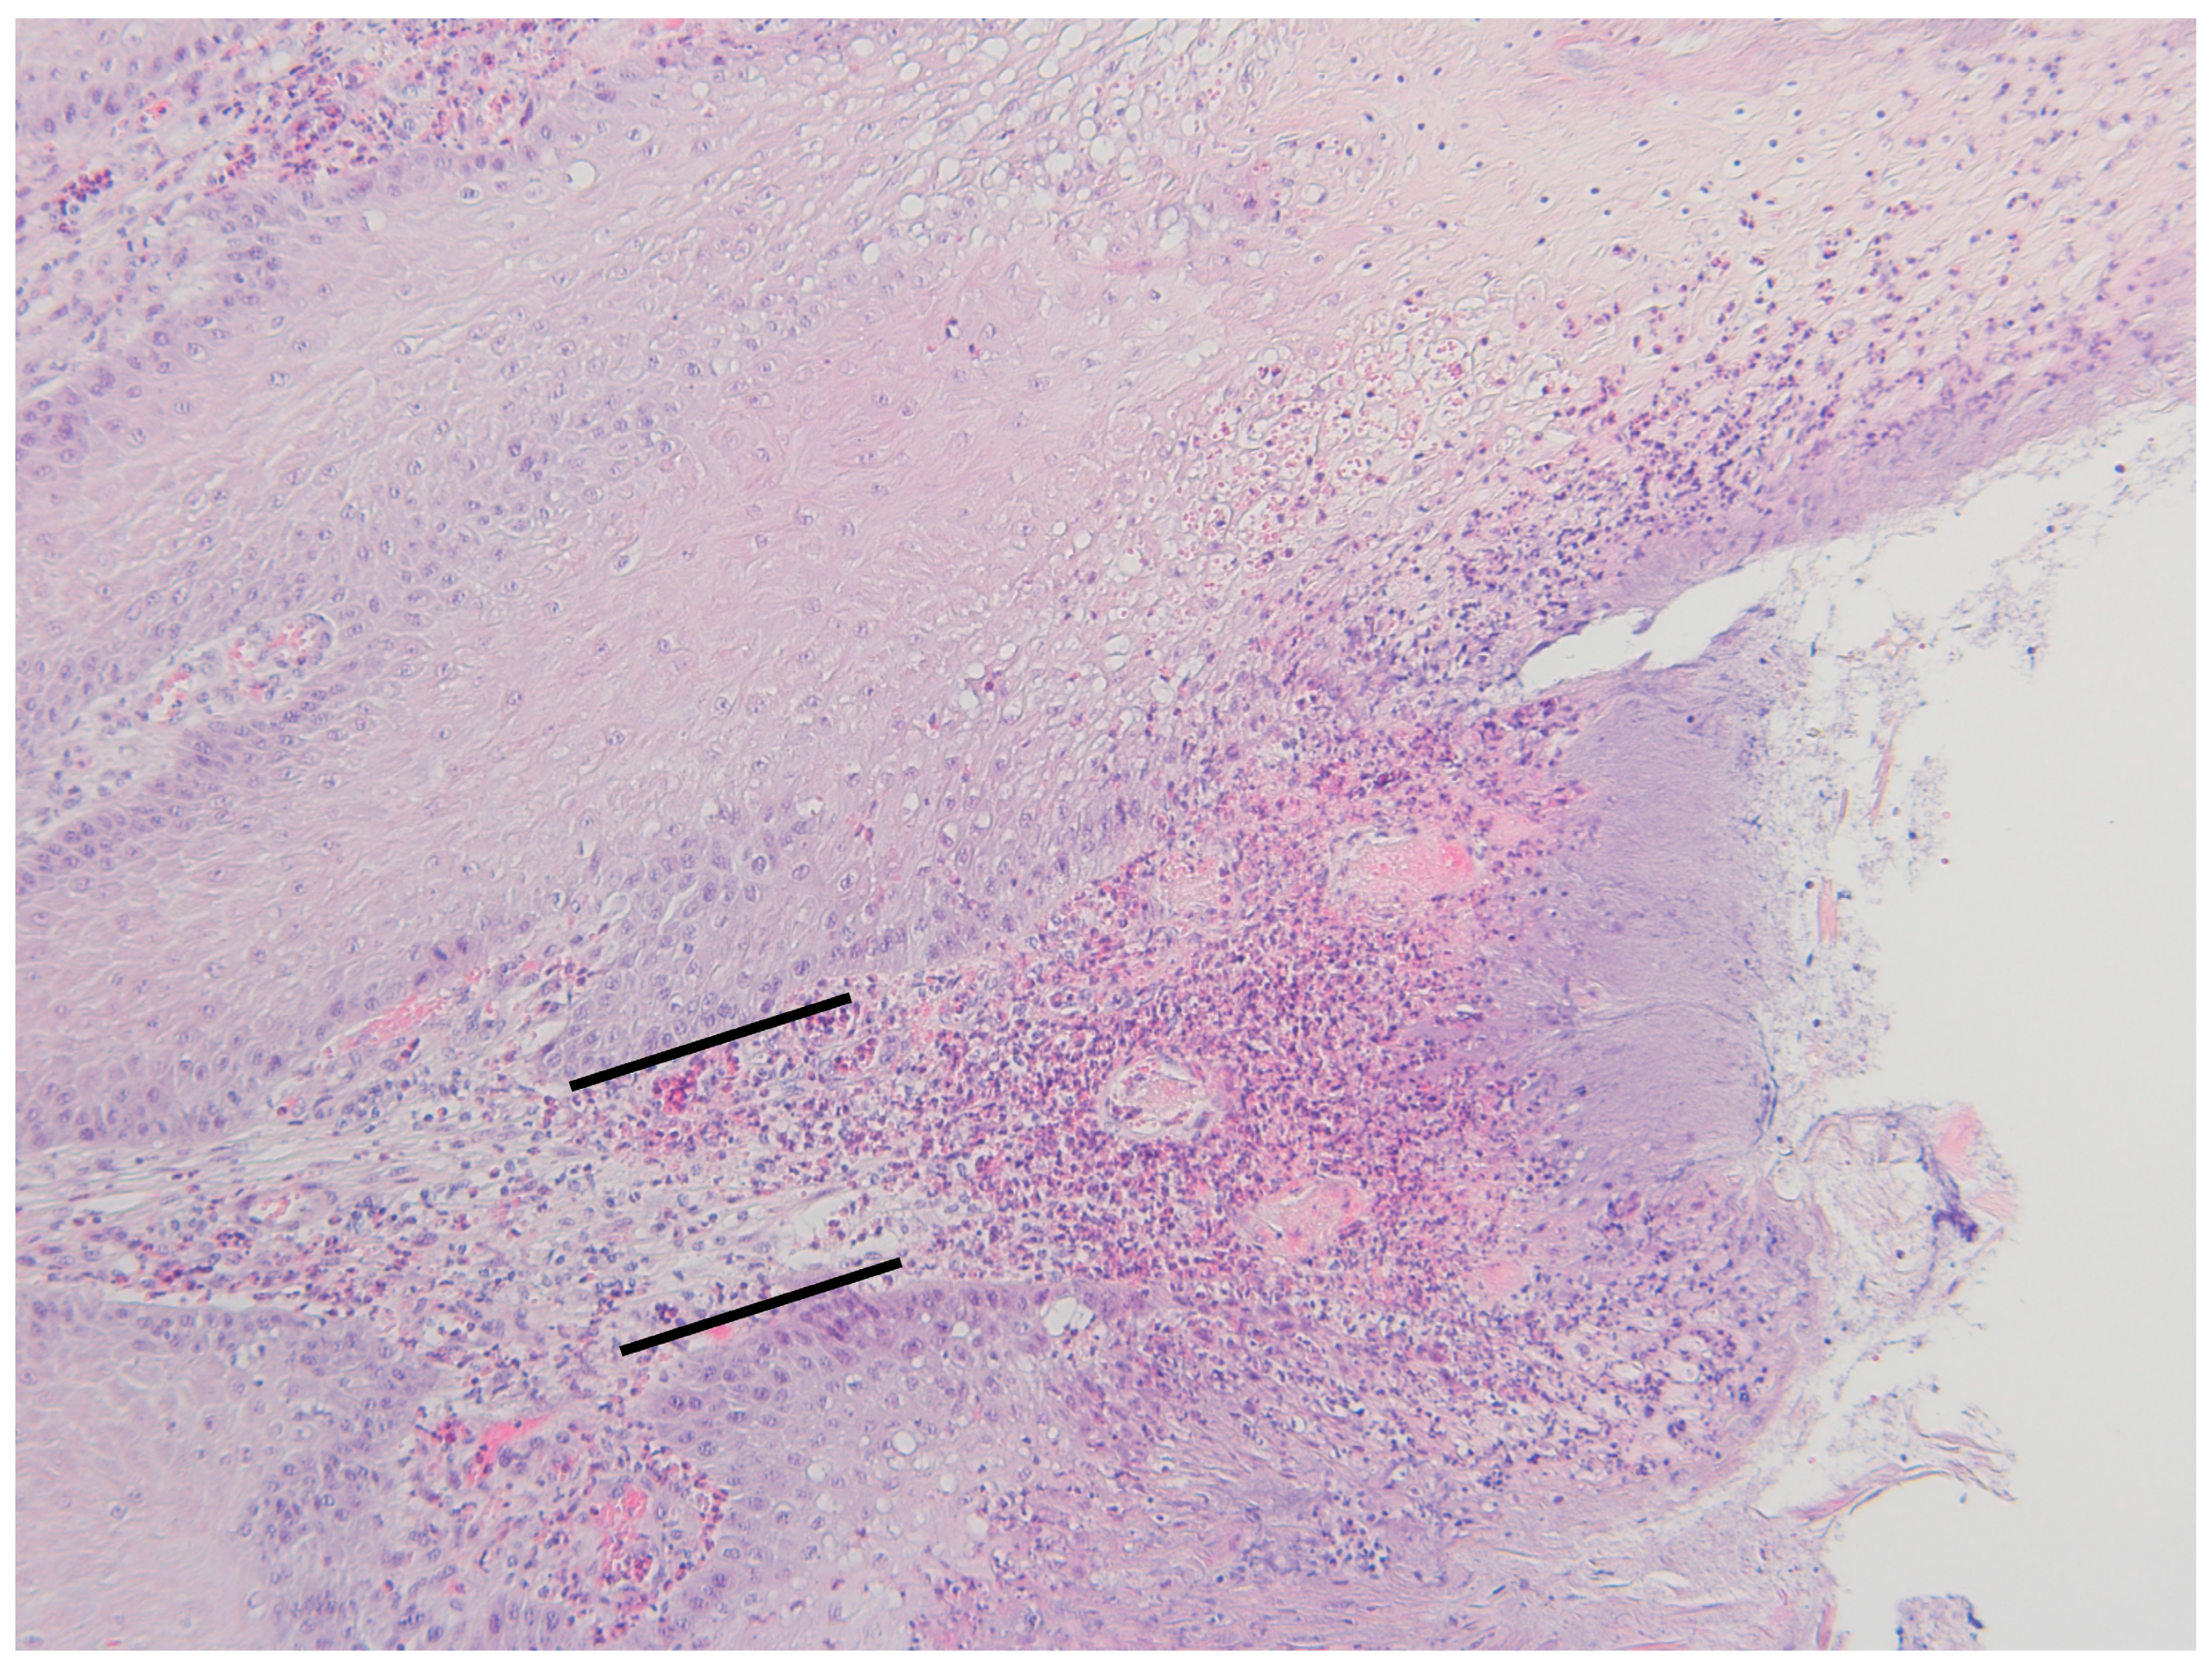

3.2. Histopathological Changes

| Grade | Description | Thickness of Epidermis (mm) |

|---|---|---|

| 0 | normal | 0.3–0.8 |

| 1 | mild to moderate hyperplasia and ortokeratotic hyperkeratosis | 1–1.5 |

| 2 | low moderate hyperplasia and ortokeratotic hyperkeratosis with necrosis and erosion | 1.5–2 |

| 3 | high moderate hyperplasia and ortokeratotic hyperkeratosis with necrosis and ulceration extending to the nonpapillar dermis | 2–2.4 |

| 4 | marked hyperplasia and (para- and ortokeratotic) hyperkeratosis with some fissures in the thick layer of keratin | 2.5–4.5 |

| 5 | marked hyperplasia and (para- and ortokeratotic) hyperkeratosis with necrosis and erosion | 4–4.5 |

| 6 | marked hyperplasia and (para- and ortokeratotic) hyperkeratosis with necrosis and ulceration extending to the nonpapillar dermis | 4–4.5 |